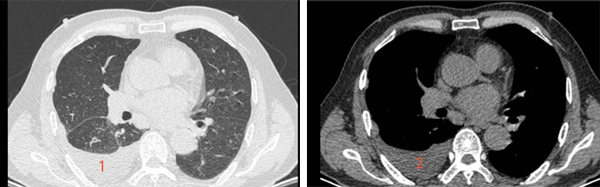

入院完善检查后,胸外科团队为患者实施“腔镜下右肺楔形切除术+胸膜活检术+腔内肿瘤热灌注治疗”,手术过程顺利。为巩固效果,术后追加两次热灌注治疗,并结合术后病理结果制定后续方案,患者顺利完成治疗后出院。术后2个月复查胸部CT显示,胸腔积液完全消失,生活质量显著改善,为后续治疗与长期管理创造了有利条件。

术后2月

3、胸腔积液消失(肺窗)

4、胸腔积液消失(纵隔窗)